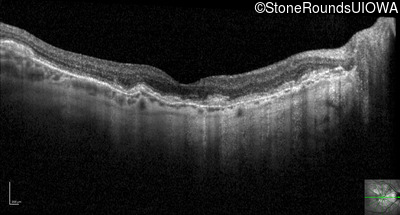

Visit at age: 62 years (Visit 3)

Optical Coherence Tomography - Right - 20/80

Exemplar / OCT Stack

OCT Stack